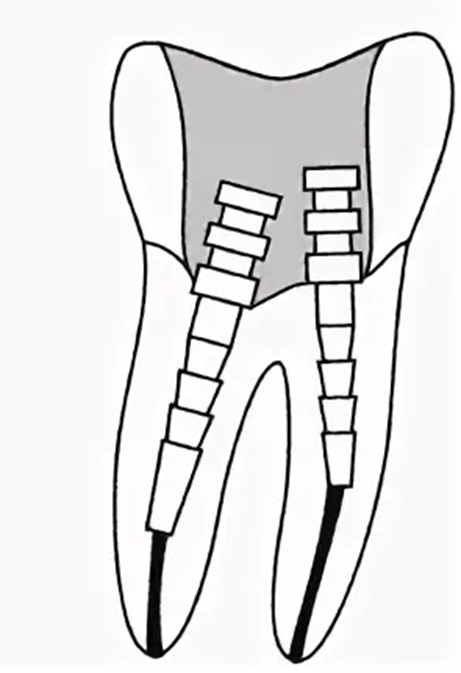

А это схематично, чтобы вы поняли.